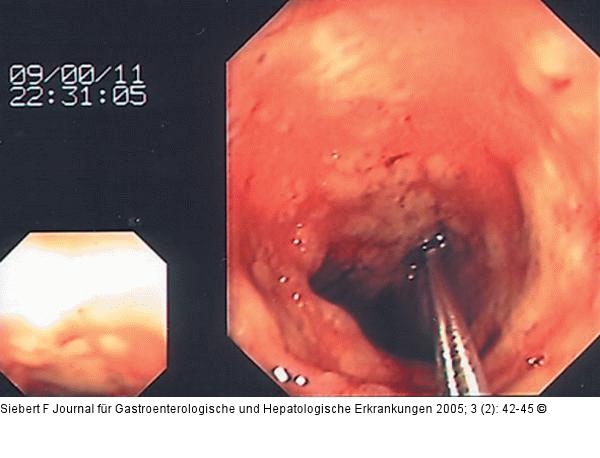

Abbildung 9a-d: Kolon-Ischämie - Differentialdiagnosen Differentialdiagnose Ischämische Colitis (oben) – Pseudomembranöse Colitis (unten) |

Abbildung 9b

Abbildung 9a-d: Kolon-Ischämie - Differentialdiagnosen

Differentialdiagnose Ischämische Colitis (oben) – Pseudomembranöse Colitis (unten) |